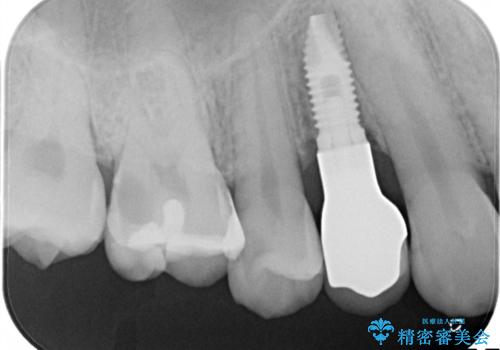

残せなくなってしまった乳歯 インプラントによる補綴